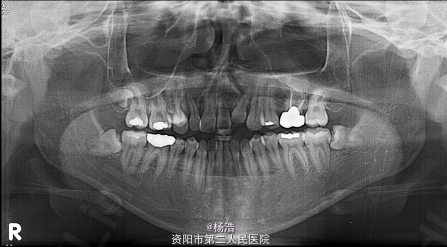

主诉:面型凹,下颌突。 女,先天性完全单侧唇腭裂,无家族遗传史,10岁时行唇腭裂修补术

面中份凹陷,下颌体长度过长,面下1/3过长。口内:安氏III类磨牙关系,前牙反合,上颌右偏,上颌第二前磨牙缺失,14牙腭侧异位,上中线右偏3mm,锥形侧切牙 全景示:原始腭裂在上颌左侧侧切牙处。 侧位片显示骨性III类,上颌后缩,离散生长型。

诊断:唇腭裂术后,骨性III类,前牙反合 治疗目标:解决面中份凹陷和上颌的偏斜,增加面部美观,调整咬合关系。 处理:先对狭窄的上颌骨进行牵张成骨,见下图所示制作装置,牵张成骨后上固定矫治器进行正合手术前正畸治疗,拔除14牙,排齐整平上下牙列,去除代偿;正合手术行LeFort I型截骨术前移上颌5mm,及BSSRO后退下颌6mm,颏成形术以减少面下部垂直高度。术后8个月精细调整,结束治疗。 上下前牙舌侧丝固定保持。 治疗后两年复查,效果依然稳定,患者满意。